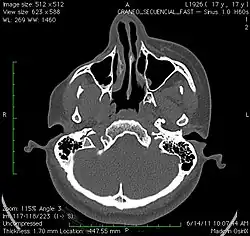

El diagnóstico se realiza basándose en los síntomas y la exploración. Se realizan pruebas complementarias como la resonancia magnética nuclear para comprobar el grado de afectación. Debe diferenciarse el mal de otras enfermedades que pueden dar síntomas parecidos, entre ellas la esclerodermia en golpe de sable, la hipoplasia facial congénita, la atrofia postradiación y la celulitis bacteriana.[1]